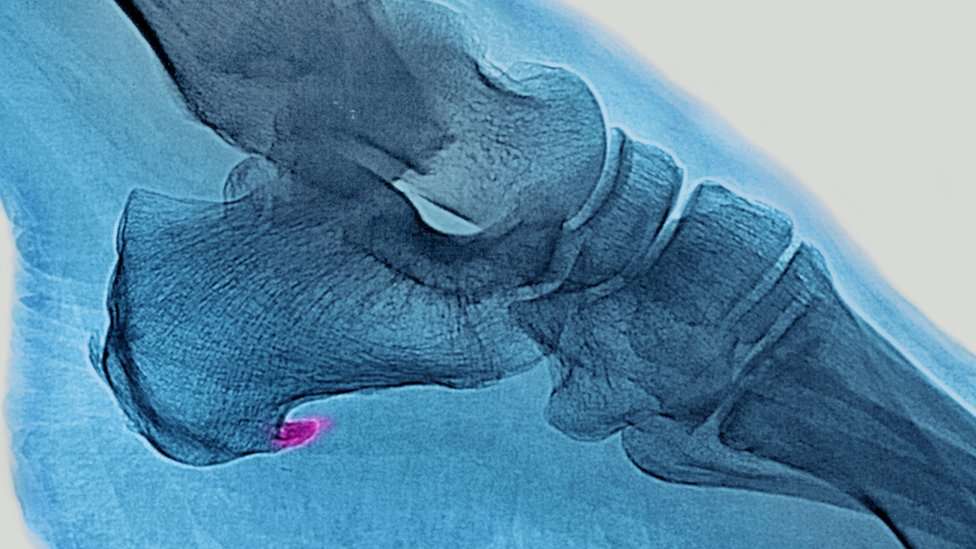

Se trata de un dolor agudo en la planta del pie, justo por delante del talón, que se intensifica cuando nos levantamos o pasamos un período de tiempo sin movernos.

Lo que ocurre es que se produce una inflamación de la membrana que recubre la musculatura de la planta del pie y el talón.

Eso se debe a que la fascia plantar cumple una función biomecánica al caminar de absorber y devolver la energía que se produce cuando el pie impacta contra el suelo.